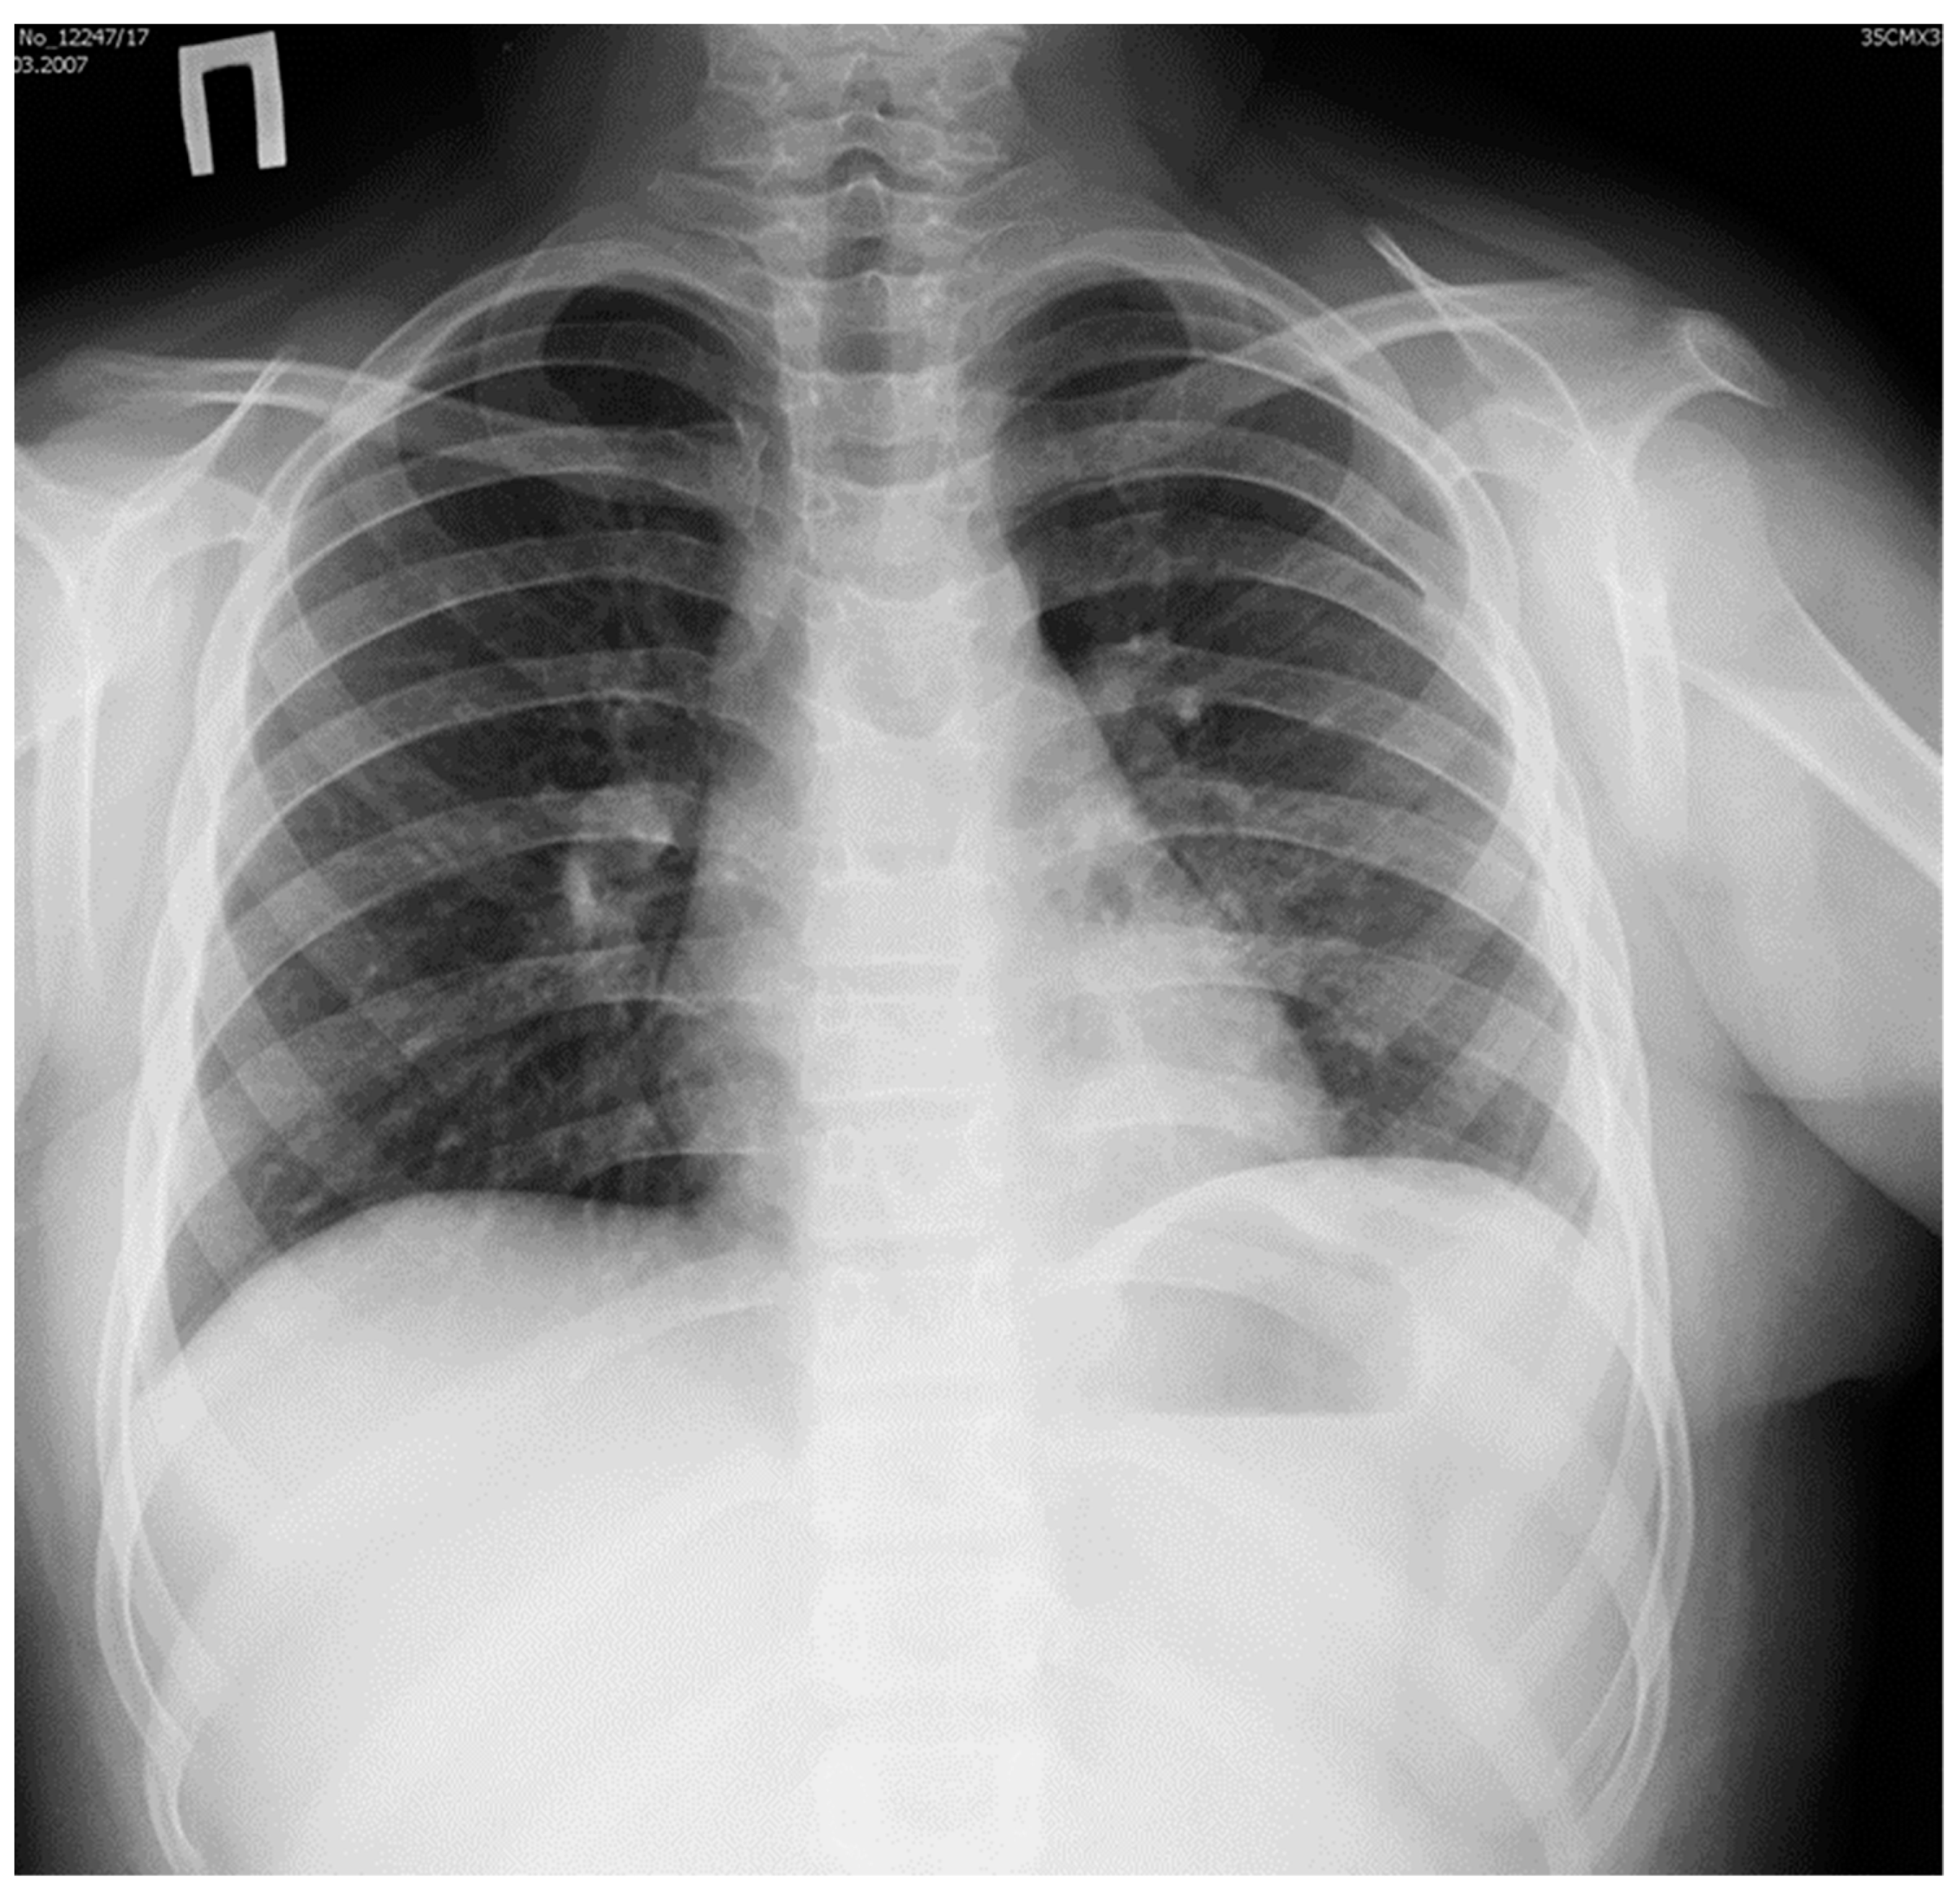

We performed multi-slice, contrast-enhanced CT scanning of the thorax and upper abdomen with subsequent multiplanar reconstruction. The lung tissue exhibited massive infiltration with cavities measuring 3 mm to 28 mm at the posterior-basal segment S10 of the left lower lobe (Figure 1).

Figure 1. CT scan of the thorax. A portion of lung tissue contained cavities (indicated by arrow) and hyperdense scar formation located in the dorsomedial part of the lower lobe of the left lung.